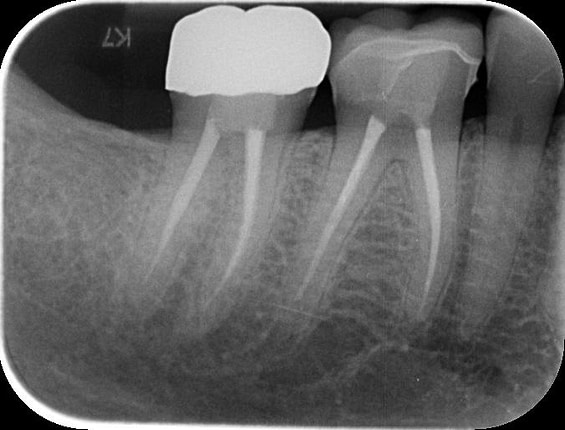

The successful completion of the implant treatment was evaluated based on aesthetics, function, and patient satisfaction.

The implant-supported crown seamlessly integrated with the patient's natural dentition, and the patient reported excellent comfort and function.

A radiographic assessment confirmed the proper integration and positioning of the implant.

The successful treatment outcome can be attributed to digital dentistry: planning, precise execution, and patient-centered approach facilitated by the digital workflow.

By leveraging advanced technologies like 3Shape TRIOS, Implant Studio, and TRIOS Design Studio, I delivered a high-quality, customized implant-supported restoration that met the patient's functional, aesthetic, and emotional needs.